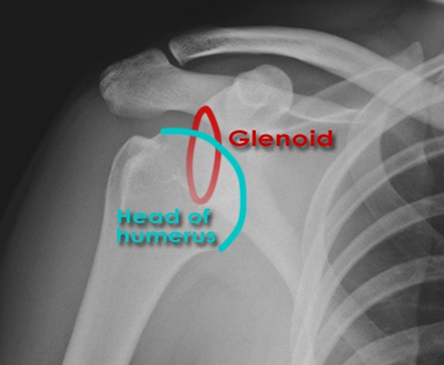

A 50-year-old patient presents with acute shoulder pain after a seizure. On examination, the arm is held in internal rotation, and the anterior shoulder appears flattened. External rotation is severely restricted. Which radiographic finding on an AP shoulder view is pathognomonic for a posterior shoulder dislocation?

Correct Answer: Trough line sign

Explanation:

The Trough line sign (or reverse Hill-Sachs lesion) is an impaction fracture on the anterior-medial aspect of the humeral head, often seen with posterior dislocations. The other options are incorrect: Hill-Sachs and Bankart lesions are typically associated with anterior dislocations. HAGL lesions are avulsions of the glenohumeral ligaments, often associated with anterior dislocations. Os acromiale is an anatomical variant.